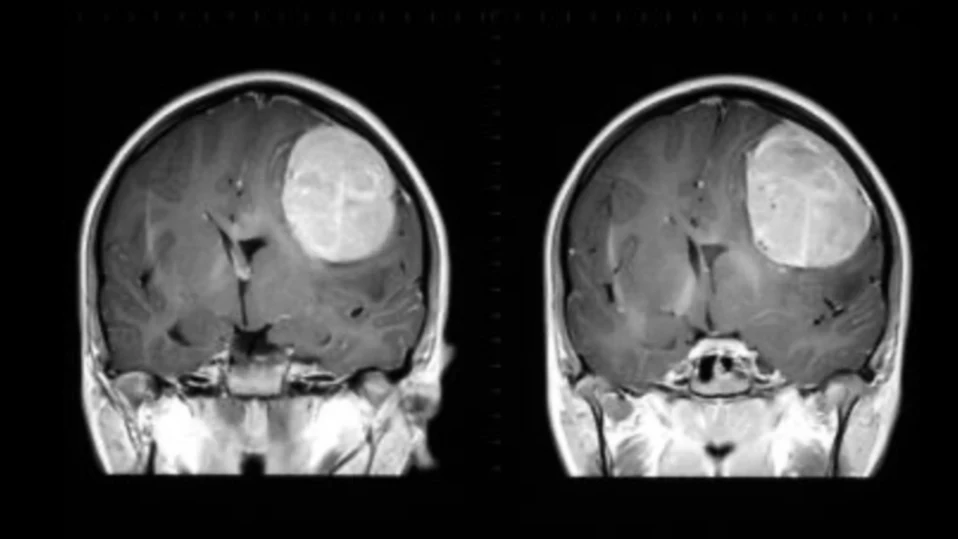

Изследователи от Вашингтонския университет и Северозападния университет разработиха нов метод за доставка на лекарства до мозъка чрез назален спрей, който потенциално може да помогне в лечението на агресивни мозъчни тумори като глиобластома, съобщава Newsweek.

В експерименти с мишки учените използвали прецизно проектирани наноструктури (сферични нуклеинови киселини, SNA), които доставят лекарство през носа и активират имунния отговор на мозъка срещу тумора. Резултатите показват, че новият метод свива туморите и „затопля“ иначе имуносупресираната туморна среда, което прави имунотерапиите по-ефективни.